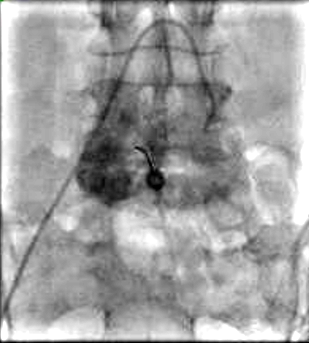

在做子宫动脉栓塞时,栓塞第二根血管就会开始疼。术后第一晚最疼,是因为组织没血了;出院前一两天又会有一个疼的过程,是因为身体在发炎清理坏死组织。这种疼痛是正常的,但需要提前和持续地用止痛药来控制。 ![]() 子宫肌瘤栓塞术后疼痛是否需要重视 Is Pain after UFE a big deal?子宫肌瘤治疗方法 由Ravina 等人1995 提出的子宫动脉栓塞术(UAE)【Ravina 1995】 美国进行了 20 万例子宫切除手术 美国进行了 30,000 例子宫肌瘤切除手术 全球约25,000子宫动脉栓塞 子宫动脉栓塞地区医疗资源未得到充分利用的一个原因在于人们对术后子宫肌层缺血性疼痛的误解。 ![]() 多中心前瞻性单臂临床试验,评估了子宫动脉栓塞术(UAE)治疗子宫肌瘤的耐受性和恢复情况。研究结果显示,大多数患者在UAE后仅需住院一晚,并能在两周内恢复。然而,术后疼痛是一个显著的问题,不仅影响了患者的恢复速度,也是导致住院时间延长的主要原因。尽管总体并发症率相对较低,但其中大部分与疼痛有关。因此,优化疼痛管理和支持措施对于改善UAE患者的恢复体验至关重要。 ![]() ![]() 强调了子宫动脉栓塞术在治疗症状性子宫肌瘤方面的安全性和有效性,并指出术后疼痛管理是影响患者选择的重要因素。作者提出了一系列简单而有效的技术和管理措施,包括血管树修剪、栓塞技术、详细的围手术期管理和骶前腹股沟神经阻滞,这些措施可以显著减少术后疼痛,改善患者体验,并促进更快的恢复。核心观点在于,通过优化疼痛管理,可以使患者在UAE后获得更好的恢复效果和更少的不适。 子宫动脉栓塞术为自己赢得了一项“疼苦手术”的名声 Uterine embolization gained the reputation as a painful procedure ![]() 这导致妇科手术医生“告诫"患者远离子宫动脉栓塞 Has led some Gyn to steer patients away UFE